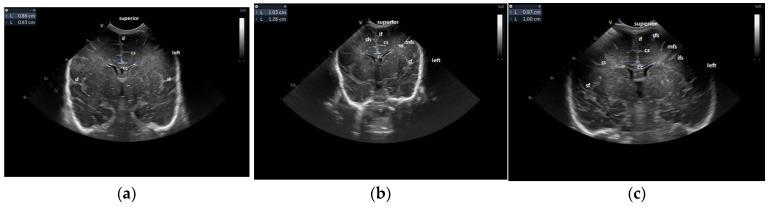

Our research aimed to assess if correlations could be found between items evaluated at the cerebral ultrasound performed at term-equivalent age (TEA) and neuro-motor outcomes evaluated at 12 and 24 months of corrected age in a group of preterm infants. The following were assessed: the Levine Index, the diagonals of the lateral ventricles, the size of the ventricular midbody, the sinocortical distance, the width of the basal ganglia, the cortical depth at the level of the cingular sulcus and the maturation of the gyral folding. The neurologic evaluation was performed at 12 and 24 months of corrected age, according to the Amiel Tison neurologic examination, and the items from the calendar of motor acquisitions were used as outcome measures of the study-gross and fine motor subsets. The comparisons between the different groups were performed using the FANOVA test, with a statistically significant association for a < 0.05. The abnormal gross motor acquisitions at 12 months were significantly associated with an increased size of the ventricular midbody ( < 0.009) and a significantly decreased diameter of the basal ganglia ( < 0.011) on the TEA cerebral ultrasound. At 24 months, a significant association was found with increased size of the ventricular midbody (>10.33 mm) ( < 0.001), a decreased diameter of the basal ganglia (<12.9 mm) ( < 0.016), a decreased cortical depth ( < 0.021) and an immature gyral maturation pattern ( < 0.001). In the case of severely abnormal fine motor outcomes, at 12 months, there were statistically significant associations with an increased size of the ventricular midbody ( < 0.001) and an immature gyral folding pattern ( < 0.0180); at 24 months, significant associations were noted with the size of ventricular midbody ( < 0.001), a decreased diameter of the basal ganglia ( < 0.016), a decreased cortical depth ( < 0.021) and an immature gyration folding ( < 0.001). The abnormal gross and fine motor outcome in former premature infants at 12-24 months corrected age is significantly associated with abnormal findings in the head ultrasound examination performed at TEA reflecting both white matter (increased midbody distance) and grey matter (decreased diameter of the basal ganglia, decreased cortical depth and an immature gyration pattern) involvement.

我们的研究旨在评估在一组早产儿中,足月等效年龄(TEA)时进行的脑超声评估项目与矫正年龄12个月和24个月时评估的神经运动结局之间是否存在相关性。评估了以下指标:莱文指数、侧脑室对角线、脑室中间部大小、脑沟皮质距离、基底神经节宽度、扣带回沟水平的皮质深度以及脑回折叠的成熟度。根据阿米尔·蒂松神经学检查,在矫正年龄12个月和24个月时进行神经学评估,并将运动发育日程中的项目用作研究的粗大运动和精细运动亚组的结局指标。使用FANOVA检验对不同组进行比较,P<0.05具有统计学意义的关联。在TEA脑超声检查中,12个月时粗大运动发育异常与脑室中间部增大(P<0.009)和基底神经节直径显著减小(P<0.011)显著相关。在24个月时,发现与脑室中间部增大(>10.33mm)(P<0.001)、基底神经节直径减小(<12.9mm)(P<0.016)、皮质深度减小(P<0.021)和脑回成熟模式不成熟(P<0.001)存在显著关联。对于严重异常的精细运动结局,在12个月时,与脑室中间部增大(P<0.001)和脑回折叠模式不成熟(P<0.0180)存在统计学显著关联;在24个月时,与脑室中间部大小(P<0.001)、基底神经节直径减小(P<0.016)、皮质深度减小(P<0.021)和脑回折叠不成熟(P<0.001)存在显著关联。矫正年龄12至24个月的前早产儿的粗大和精细运动异常结局与TEA时进行的头部超声检查中的异常发现显著相关,这反映了白质(中间部距离增加)和灰质(基底神经节直径减小、皮质深度减小和脑回模式不成熟)均受累。